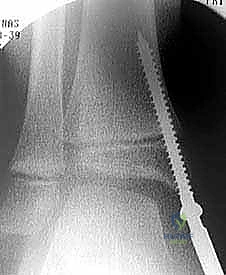

الخطوة الثانية: التوجيه بالأشعة التلفزيونية (Fluoroscopy)

يستخدم الدكتور هطيف جهاز الأشعة السينية المتحرك (C-arm) داخل غرفة العمليات لتحديد موقع الغضروف المشاشي (مركز النمو) بدقة متناهية بالملليمترات، دون الحاجة لفتح جراحي كبير.

الخطوة الرابعة: تثبيت الشريحة (8-Plate)

بمهارة فائقة، يقوم الدكتور هطيف بوضع الشريحة المعدنية المصنوعة من التيتانيوم الطبي النقي فوق مركز النمو. يتم تثبيت الشريحة باستخدام مسمارين صغيرين؛ أحدهما فوق خط النمو والآخر تحته. هذه المسامير لا تخترق مركز النمو نفسه، مما يضمن عدم تدميره.